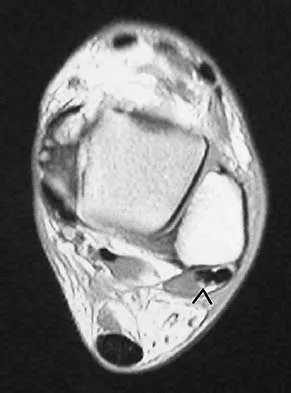

Question 85

Figure 24 shows an axial MRI scan of the ankle. The arrowhead is pointing to what structure?

Explanation